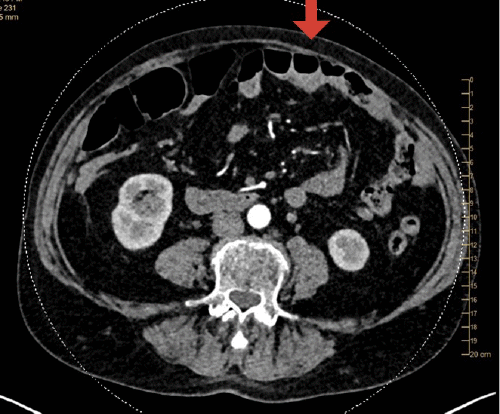

The patient complained of persistent pain in the abdomen with distention, a bulge in the upper abdomen, difficulty standing upright, and difficulty taking a deep breath since the time of her breast reconstruction surgery. On physical exam, an abdominal bulge was apparent on stress testing in the epigastrium and left hemi-abdomen. CT scan of the abdomen and pelvis demonstrated asymmetric abdominal wall musculature consistent with her previous TRAM flap but no evidence of a hernia (Figure 1).

Figure 1. Abdominopelvic CT Scan. Published with Permission

Left rectus abdominal musculature smaller than right consistent with left pedicled transverse rectus abdominis muscle (TRAM) flap surgery. No anterior abdominal wall hernia or mass